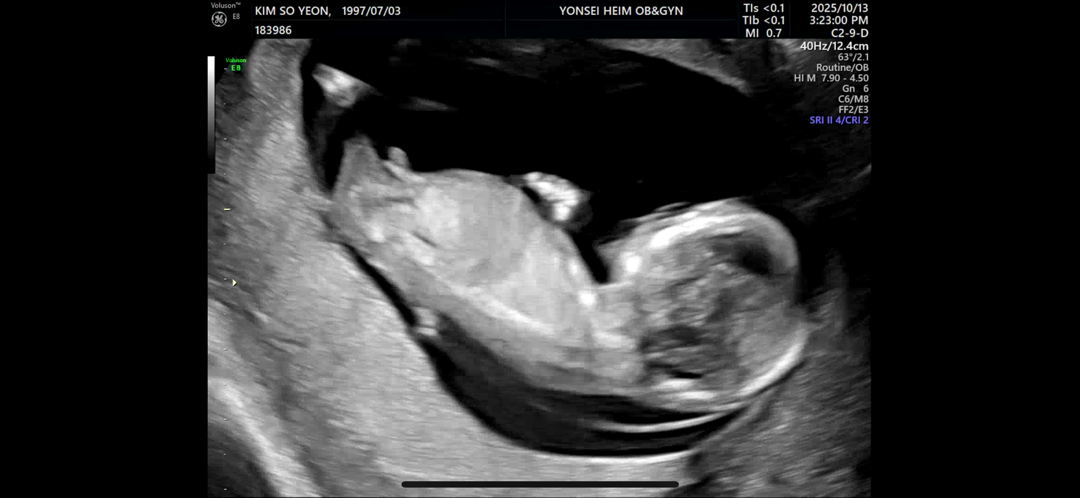

저희 다복이 남아같나요 여아같나요? Ai로 확인했긴한데... 배동님들 의견도 궁금하네요🥰